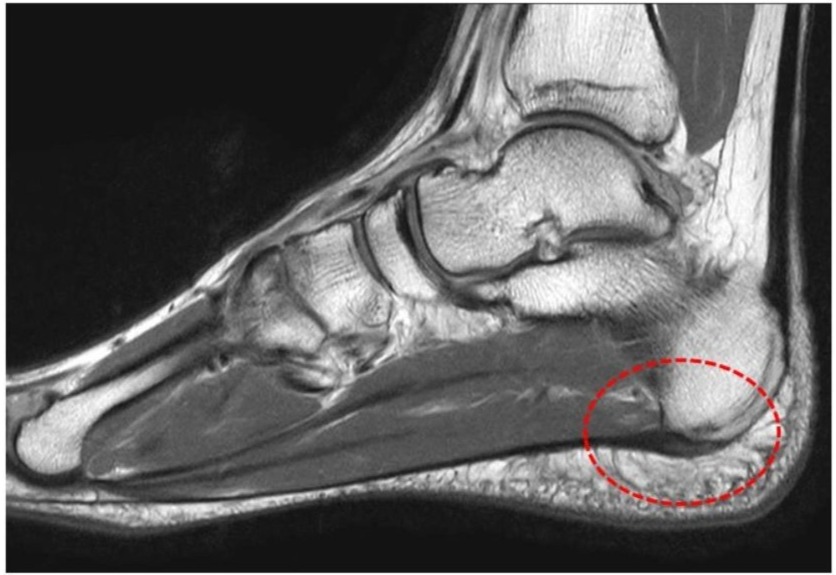

足の裏には、「足底腱膜(そくていけんまく)」という、かかとの骨から足の指の付け根まで伸びる膜状の組織があります。足底腱膜は足のアーチ(土踏まず)を支えて、衝撃を吸収して、足を安定させる役割があります。足底腱膜炎とは、足底腱膜のかかと側の付着部で炎症が起きて、痛みを生じた状態をいいます。主に荷重時の痛みであり、起床時の最初の1歩が最も痛いと訴えられる患者様が多いのも特徴です。足底腱膜炎は40~60代の方、高体重、ランニングなどで足に負担がかかりやすい方、扁平足傾向(足の土踏まずが潰れてしまっている状態)、足関節の柔軟性低下などが発症のリスク因子とされています1)2)3)。患部へ負担がかかり続けると、足底腱膜が分厚く変性(肥厚)、骨のトゲ(骨棘)の発生、腱内部の異常血管の侵入や痛みを知覚するための神経線維の過剰な増加などの変化が起こり、痛みの改善までに時間がかかる場合があります。(図1,2)。

図2 足底腱膜の変性が見られるMRI画像